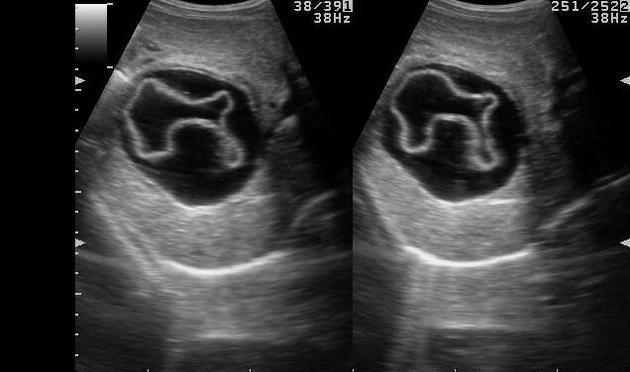

Sheep herder

Echinococcal Cyst

Sheep Herders

AKA Hydatid Cyst

Sheep herder

Echinococcal Cyst

Sheep Herders

AKA Hydatid Cyst

Water lily

Sheep herder

Echinococcal Cyst

Sheep Herders

AKA Hydatid Cyst